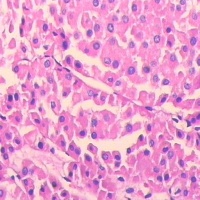

肾移植切片病理

肾移植是治疗尿毒症比较有效的方式,到现在为止,肾移植手术的成功率并不算很高。并且手术后的排异性并没有得到很好的解决。

在夫妻间实施的肾移植,明显高于尸体供肾移植的存活率。

夫妻间供肾移植的存活率等同于有血缘关系的亲属活体供肾移植,因为长期生活在一起的夫妻,在生活环境、饮食习惯上很相似,而且因为性生活的密切接触,生育过子女之后,双方体内就会有抗原的交换,细胞的嵌合,组织有相容的地方,从而形成免疫耐受,手术后排异性小。